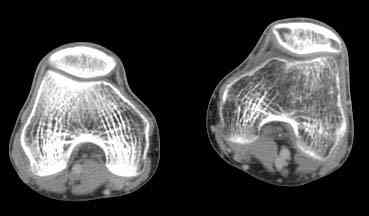

важаемые коллеги! Поступил больной 22 лет. Болен с января 2006 - появились боли в области верхнейтрети голени. При первичном осмотре в поликлинике был заподозрен первично-хронический остеомиелит - осмотрен гнойным хирургом - произведена биосия . Заключение - хондросаркома. Осмотрен онкологом - с учетом характера опухоли - химиотерапия, лучевое лечение не показано. Предложена либо ампутация, либо решение вопроса о возможности выполнения органосохраняющей операции. При обращении к нам произведена сцинтиграфия скелета - зоны гиперфиксации РФП: верхняя треть голени- 960%, нижняя треть бедра - 380%, Дистальный метафиз голени и затылочная область - 140%. В легких - метастазов нет. Произведена КТ (картинки в приложении). Учитывая абсолютную нестыковку рентгенологических и морфологических данных повторно биопсия. Выявлено, что первичная биопсия выполнялась из поверхностной параоссальной зоны - там локализованы хрящеподобные массы, далее очень плотная кость без хрящевых участков - биоптат взят фрезой с большим трудом. Морфологического заключения пока нет. Хотелось бы узнать Ваши варианты диагноза и соответственно тактику.